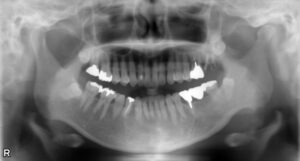

上顎大臼歯2本欠損症例

BEFORE AFTER 50歳女性/上2本欠損/インプラント埋込手術 【治療内容】 左上第一大臼歯、第二大臼歯は他院で…